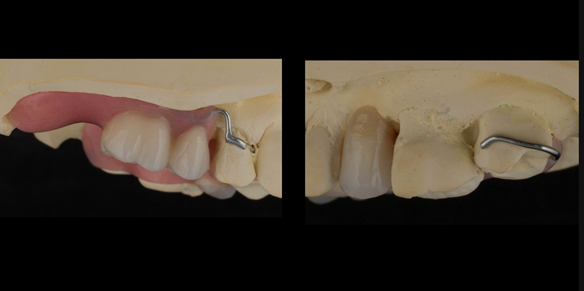

This newsletter describes in step by step detail Angela's transition through immediate partial dentures to crown supported definitive metal based dentures.

The clinical situation and treatment process is shown in detail below with photographs. I (Finlay Sutton) provided the clinical work and Rowan Garstang provided the technical work.